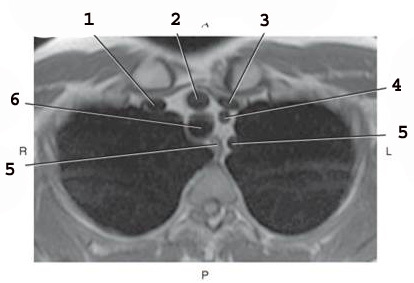

1

L common carotid Artery

2

L subclavian artery

3

AO arch

4

ascending AO

5

SVC

6

Brachiocephalic trunk